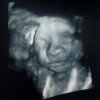

Ooooh dzien dobry cukiereczkuJa dziś jestem po wizycie. Mały jest główka do dołu nareszcie. Wiem że może się przekręcić ale to pierwszy raz od początku ciąży że jest głową w dół więc się ciesze. Ogólnie jest w porządku. Waży już 1150g.

Zobacz załącznik 1197077

ŚlicznosciJa wczoraj byłam u lekarzamała waży juz 1,8kg i też jest już obrócona główka w dół.